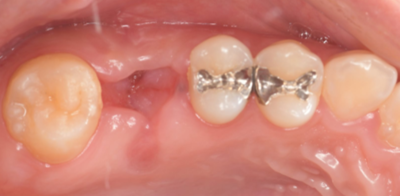

右上6抜歯後

右上6(青丸)を抜歯し、右下8(赤丸)を移植することを計画した。

右上の抜歯後の治癒を待つため、抜歯の1ヶ月後に移植を行うこととした。